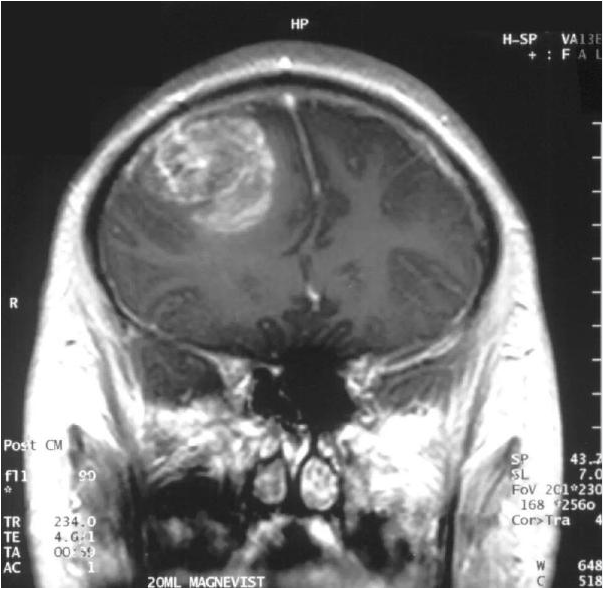

胶质母细胞瘤是一种恶性脑肿瘤,极难治疗。据估计,在确诊后,约一半的患者只能活上 1 -1.5 年。不幸的是,我们非但没有治疗这种疾病的好方法,甚至连它背后的原因都没有摸清。目前,生物学家们知道有超过 223 条基因和这个疾病有关。但我们不知道哪几条基因,或者是哪些基因的组合会导致这些癌症。这也是 Chen 教授团队的研究重点。

▲胶质母细胞瘤这种顽疾,有望迎来个体化的治疗方案(图片来源:维基百科)